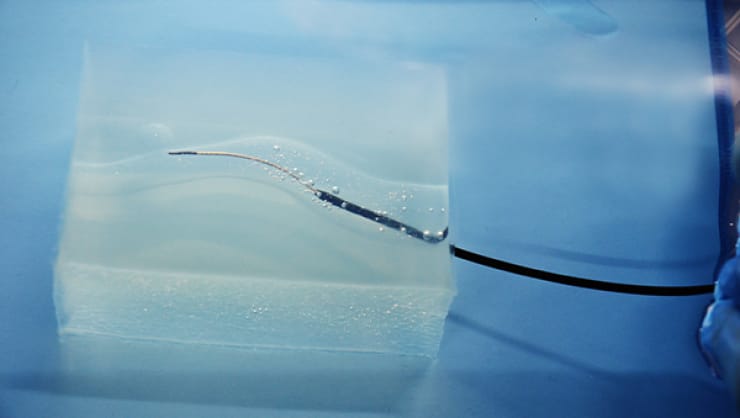

滑り性×透明

摩擦抵抗が低いため、デバイスをモデル内に通過させる際、生体と近い操作感を得ることが可能。高透明材のため、目視下でも、デバイスの挙動確認ができる。